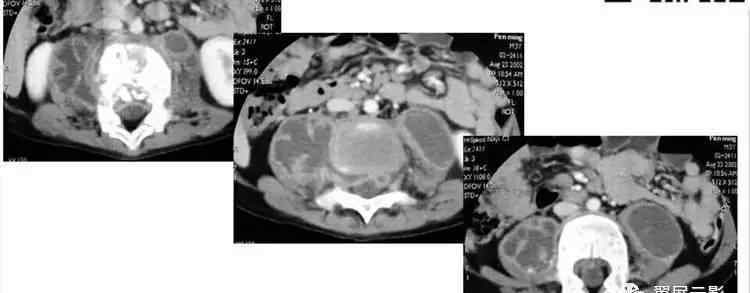

该病例的特征为腹膜后肿瘤、Tiwi+FS信号、液-液平面、T2WI+FS高信号、动态增强减影无强化

病理结果:异位支气管囊肿可见平滑肌细胞纤毛柱状上皮

最后我们总结一下:1。异位支气管囊肿:先天性,多见于腹膜后左侧,圆形/类圆形,薄壁单间,壁强化,t1信号强度相等或稍高,T2信号强度高,液面高。2.囊性畸胎瘤常见于女性新生儿左侧,呈圆形/类圆形,薄壁,单房或多房,壁无强化,成分复杂不均匀,也有脂肪分层。3.儿童囊性淋巴管瘤,生长在任何位置,薄壁,有或无间隔,均匀,低信号强度的钛和高信号强度的T2。4.中肾管/副中肾管囊肿年轻女性,圆形或类圆形。单间/多间,墙略厚且均匀,ti低信号,T2高信号。可能有激素刺激异常史。5.淋巴囊肿、泌尿囊肿、血肿、脓肿。有外伤史,泌尿系囊肿多见于肾脏周围。这些病变有各种形状,取决于病变的位置、性质和内容,并有相关病史。